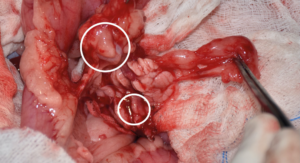

El tratamiento quirúrgico es el de elección para perros con enfermedad en estadio I (enfermedad localizada) o II (presencia de metástasis locorregional) e implica una pancreatectomía parcial para extirpar el tumor primario y cualquier metástasis visible (imágenes 4A-4K y 5A-5H). La mediana de supervivencia es más larga en los perros tratados quirúrgicamente en comparación con los perros tratados médicamente, como se describe en dos estudios donde la mediana del tiempo de supervivencia de los perros sometidos a pancreatectomía parcial fue de 381 días y 785 días, respectivamente, en comparación con 74 días y 196 días, respectivamente, en aquellos tratados solo con tratamiento médico.30 En otro estudio reciente, el tiempo medio de supervivencia registrado para 49 perros con insulinoma fue de 561 días y de hasta 746 días para perros que tuvieron resolución de hipoglucemia, con un tiempo medio euglucémico global (tiempos desde la cirugía hasta la primera detección de hipoglucemia en cualquier momento después de la cirugía) de 424 días para todos los perros.39

Imágenes 4A – 4K. Secuencia de imágenes quirúrgicas en un perro (con las imágenes del TC), durante una pancreatectomía total del lóbulo izquierdo y cuerpo del páncreas (usando la técnica de “guillotina” sutura/fractura con el nudo de Miller modificado) y resección de NNLL centinelas, por insulinoma en el cuerpo del páncreas.

Imágenes 5A – 5H. Secuencia de imágenes quirúrgicas en un perro (con las imágenes del TC), durante una pancreatectomía total del lóbulo derecho y parte del cuerpo del páncreas (usando la técnica de “guillotina” sutura/fractura con el nudo de Miller modificado) y resección de NNLL centinelas, por insulinoma en el lóbulo derecho del páncreas.